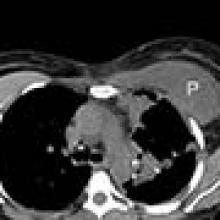

[3]A. CT thorax showing the right implant in situ and the left implant capsule filled with pleural fluid (P).

B. The hyperdense left implant in the posterior pleural space (*) was misreported as hemothorax.

She returned to the emergency department twelve days later with pleuritic chest pain, nausea, and a low grade fever. A CT scan of the chest showed a high-density pleural effusion consistent with hemothorax. Since the patient was hemodynamically stable with no significant change in hemoglobin level, a pleural catheter was placed as the initial management. However, the effusion failed to resolve and further review of the imaging revealed that the left breast implant was no longer in the subpectoral position. What had been reported as blood in the pleural cavity was in fact the implant itself (Figure 1). The patient was brought to the operating room that day for VATS extraction of the implant and drainage of the pleural space. A Jackson-Pratt drain was inserted in the left breast implant capsule. She developed left mastitis post-operatively which was successfully treated with antibiotics and she was discharged five days later with follow-up with both thoracic surgery and plastic surgery.